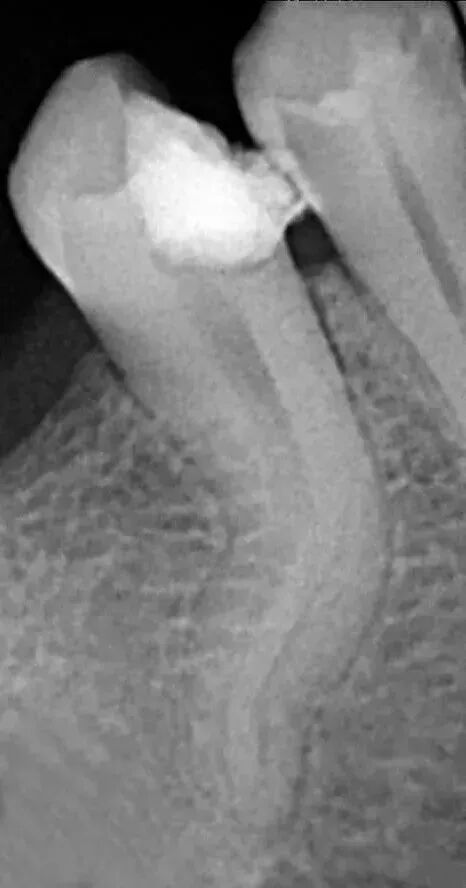

充填时机,无自觉症状,无明显叩疼,根管内无异味,无渗出,无急性尖周炎症状即可充填,不必等到所有症状消失,反复的封药容易对尖周造成大大刺激。充填的方法,质控标准:

a、充填物距根尖小于等于2mm。

b、充填致密,连续,锥度合适。

c、充填完毕烫牙胶尖根管口下2~3mm,小号充填器冷加压。

d、对于欠充患者需重新预备充填,而超充原则上不建议重做,随访,必要时根尖手术治疗。目前研究表明,在其他因素相同的前提下,超充的预后差于欠充。